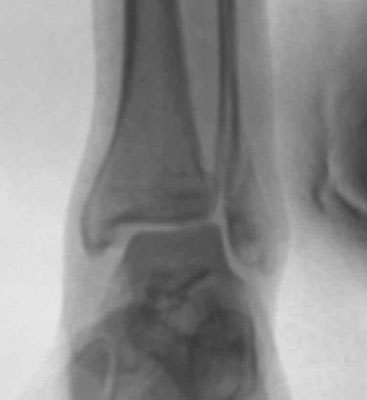

Im günstigsten Fall entsteht nur eine Verstauchung des Sprunggelenks mit Dehnung und Zerrung der Gelenkkapsel oder ein Riss der Bänder, die das Sprunggelenk stabilisieren (Außenbandriss). Bei den Knochenbrüchen handelt es sich fast immer um eine Kombination aus Knochenbrüchen und Verletzungen des Kapsel-/Bandapparates (Syndesmosenband, Innenband). Diese Kombinationen führen zu einer Instabilität der Sprunggelenksgabel mit Fehlstellung. Einfachste und häufigste Form ist der Bruch des Außenknöchels. Bei schwereren Verletzungen kommen Brüche des Innenknöchels und des sog. hinteren Knöchels dazu. Man spricht dann von „Zwei- oder Dreiknöchelbrüchen“ (Bimalleolär/Trimalleolär). Bei Zertrümmerung der Gelenkfläche des Schienbeins spricht man von einem „Pilon tibiale“.

Unverschobene und stabile Brüche können durch eine Stabilisierung im Gips oder Spezialschuh zur Ausheilung gebracht werden. Instabile und verschobene Brüche müssen operativ eingerichtet und stabilisiert werden, da es sonst durch Inkongruenzen und verbliebene Fehlstellungen zu einem schnellen Verschleiß (Arthrose) des Gelenkes kommt. Entscheidend für den Operationserfolg ist, das das sog. Sprungbein (Talus) wieder stabil und zentriert in der Sprunggelenksgabel geführt wird.